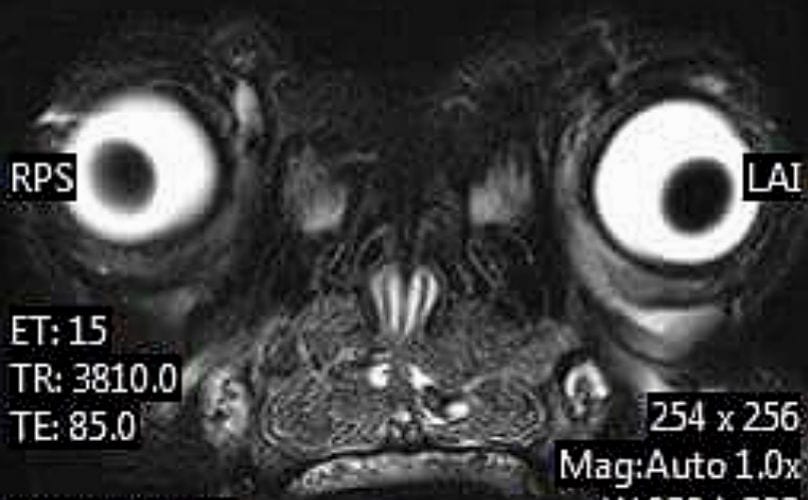

And just in case you weren't sure what you're looking at, it's a dog brain!

Each of the light orbs represents the dog's eyes, and the grey mushy mess in between is the actual BRAAAAAIIIN!

Who knew that all the precious awkwardness of a Frenchie would be just as apparent from a brain scan as it would be from an Instagram photo.